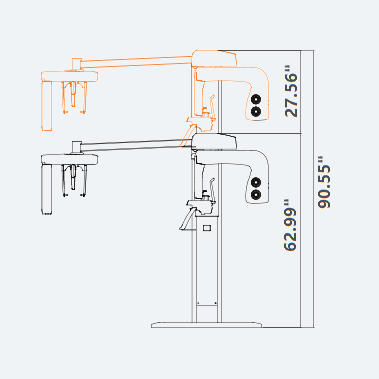

| TUBE VOLTAGE/CURRENT | WEIGHT | DIMENSIONS |

|---|---|---|

| 60 ~ 99 kV / 4 ~ 10 mA | With Ceph unit : 120 kg (264.5 lbs. – without Base) | With Ceph unit : 75.99 in (L) x 47.24 in (W) x 90.55 in (H) |

| TOP VIEW | FRONT VIEW | |

|---|---|---|

|

PaX-i RC (Rapid Ceph) |

|

|